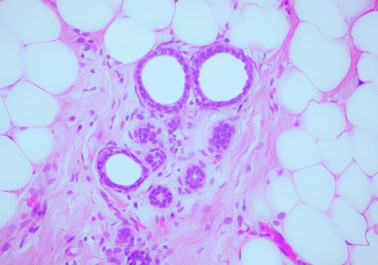

In the microscopic image, life and death form a disturbing spectacle –beautiful and terrifying at the same time. The movement of cells, the processes of their growth and decay, captured in a photograph or on film, reveal the paradox of existence: to see life, one must frame it, and often also deprive it of its existence. Both Małgorzata Lisowska's exhibition and the screening of biological films from the Educational Film Studio in Lodz archive focus on this tension, visible on a microscopic scale. In Lisowska's images, cancer cells reveal their dual nature – a drive to multiply that simultaneously leads to destruction. The films, capturing processes in the microscopic world, demonstrate a similar dynamic: life and death intertwined in the rhythm of film frames. Photography and film become tools that allow us to see this contradictory yet inextricable relationship.

The process of neoplasia reveals a fundamental paradox – the intertwining of life and death. The neoplasticity of cells expresses their desire for life and multiplication. However, it is their chaotic growth that ultimately leads to destruction. On the other hand, the death of cancer cells opens the way to life. Their elimination by the body's defence mechanisms or therapeutic interventions restores balance and allows life to continue. Thus, in the process of neoplasia, death and life are mutually dependent, creating a constant movement of opposites taking place in the body.

Małgorzata Lisowska is a microscopic photographer. She is the winner of the prestigious Nikon Small World 2023 competition with a photo of her own cancer cells – Poland's first return to the podium after 31 years. She is the author of the exhibition "History Written in the Body in Three Acts," presented at venues including the National Health Fund.